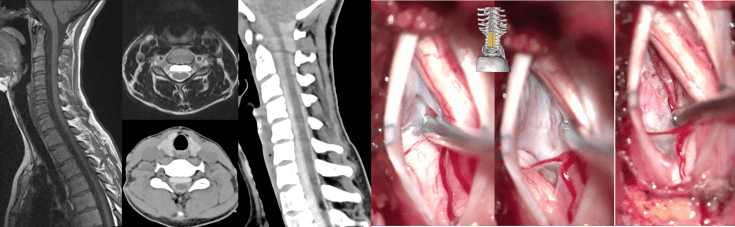

les méningocèles pré-médullaires cervicales

elles correspondant à un dédoublement de la dure-mère cervicale analogue à celui retrouvé dans les hernies médullaires au niveau thoracique ; ci-dessous, méningocèle pré-médullaire cervicale révélée par des douleurs lors des sports ; la myélographie montre un remplissage par le haut ; abord postéro-latéral pour fenestration de la partie basse de la méningocèle.